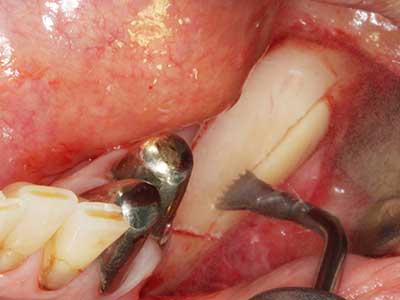

Abb. 3: Die basale Abtrennung des Blocks wird durch speziell abgewinkelte Aufsätze erleichtert.

Abb. 18: Präparation eines Kortikalis-Deckels mit der Piezo-Knochensäge (Piezomed, W&H).